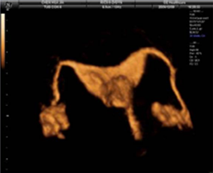

Àڱà ³ªÆÈ°ü Á¶¿µ °Ë»ç

ÀÚ±ÃÀ¯Âø, ÀڱñâÇü, Àڱð³» Á¾¾ç ¹× ³ªÆÈ°üÀÇ ¸·Èû µîÀ» È®ÀÎÇÏ´Â °Ë»çÀÔ´Ï´Ù.

Àڱó°üÁ¶¿µ °Ë»ç ¹æ¹ý

| Àڱó°üÁ¶¿µ ÃÊÀ½ÆÄ | ³ªÆÈ°ü X¼± Á¶¿µ¼ú | |

|---|---|---|

| ½Ã¼ú½Ã±â | »ý¸® Á¾·á ÈÄ 2~3ÀÏ À̳» | |

| ¹æ»ç¼±³ëÃâ | X | O |

| ÅëÁõ | X | O |

| º¸ÇèÀû¿ë | X | O |

| ½Ã¼ú½Ã°£ | 10~20ºÐ | 1½Ã°£ |

| ³»¸·¿ëÁ¾Áø´Ü | ½±´Ù | ¾î·Æ´Ù |

|  |  | |